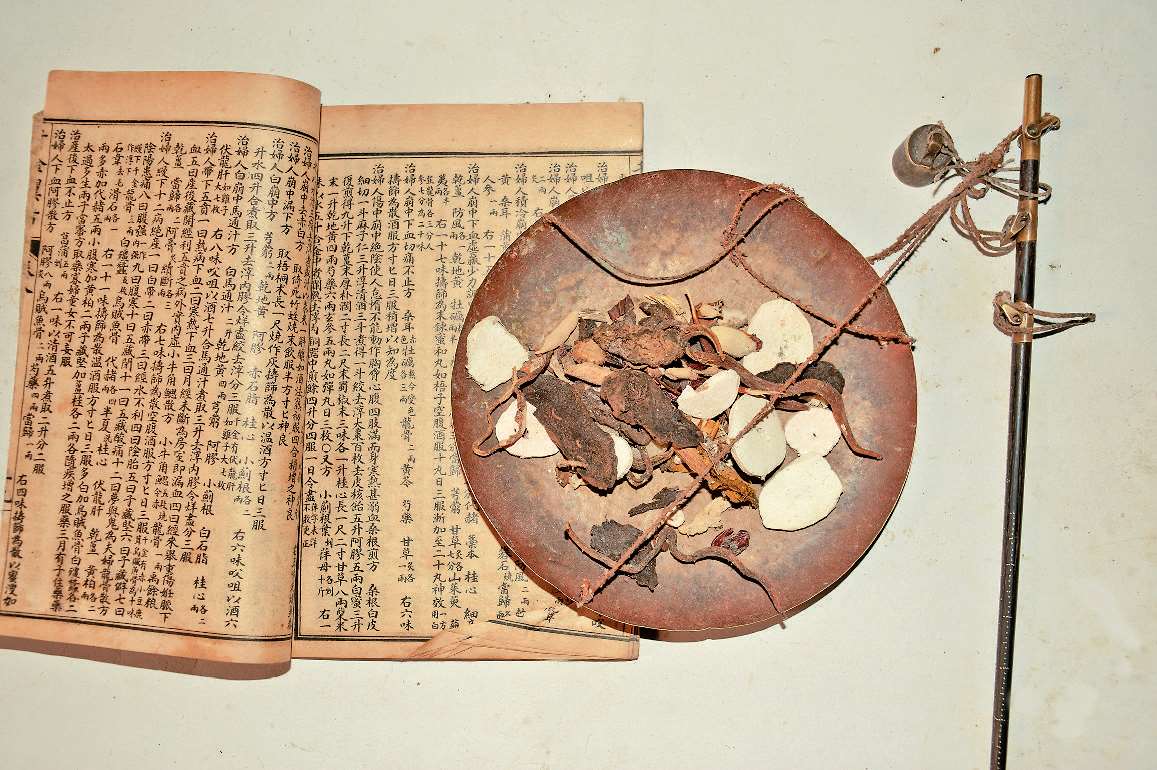

流感大流行是现代医学术语,中国古代将外感疫疠邪气所引起的,具传染性及流行性的一类疾病统称为疫病。关于疫病的记载,最早可以追溯到殷商时期的甲骨文,称“疾年”。在有文字记载的3 000多年中,最严重的瘟疫发生在东汉建安年间(196~220年),史称“建安大瘟疫”。据史料记载,此次疫情持续30余年,死亡人数近1 000万,正如曹植《说疫气》文中所载“家家有僵尸之痛,室室有号泣之衰,或阖门而殪,或覆族而丧”。可见当时疫病横行时的惨状乃历史罕见。疫病的接连发生让中国古代医家积累了丰富的抗疫经验,并总结出了《伤寒杂病论》《温热论》《解围元薮》《疯门全书》《温病条辨》等一批医学典籍流传至今。

疫病的历史源远流长,自有文字记录以来,疫病的发生成百上千,而中医学的发展历史,也可以看作为一部与疫病斗争的历史。其实早在甲骨文时期就有了关于疫病的相关记载,但受限于当时的认知条件,古人先认为疫病是由鬼神引起的,随着中医学的进步,人们开始认识到疫病是由自然界中的一种具有强烈致病性和传染性的病邪所引起。如《黄帝内经》中就已记载“五疫之至,皆相易染,无问大小,病状相似”,后人称之为“疠气”“疫气”“戾气”“杂气”等,这种病邪多从口鼻进入人体而致病,并且发现疫病的发生与自然界气候的异常变化密切相关,即所谓的“非其时而有其气”。

随着中医学的发展,诞生了许多治疗疫病的著名医家,他们在防治各种感染性疾病方面做出了杰出贡献。

被誉为“医圣”,是东汉末年的著名医学家。在疫病流行的年代,他深入钻研古籍并广泛搜集医方,最终写成了《伤寒杂病论》这部医学巨著。该书系统地总结了外感病的原因、症状、发展规律以及治疗方法,并创立了六经辨证体系,为后来的疫病治疗提供了重要的理论基础。

晋代的著名医学家和道家人物。他不仅对道家理论有着深入的研究,还对医学和疫病治疗有着独到的见解。他的著作《肘后备急方》是中国历史上第一部“抗疫应急手册”,其中记录了许多简便实用的防治瘟疫的方法,而屠呦呦“青蒿素”的发现就是从中得到了启发。此外,书中所创制的“黄连解毒汤”传用至今,还记载了“老君神明白散”“太乙流金方”等方剂,是我国最早出现的预防与治疗疫病的专方。

唐代的著名医药学家,被后人尊称为“药王”。他一生致力于医药学研究,特别是在疫病防治方面有着卓越的成就。他的著作《备急千金要方》和《千金翼方》中,详细阐述了各种疾病的预防和治疗方法,其中包括瘟疫,尤其是明确区分了伤寒、温病及温疫,书中所载“犀角地黄汤”“紫雪丹”等方剂至今仍是治疫之良方。他强调预防为主,提倡个人卫生和公共卫生,并提出了许多实用的预防措施。

明末清初传染病学家。明末清初战乱和疫病频发,他通过自己的临床实践和深入研究,提出了其成因的“疠气”致病说,认为“瘟疫之为病,非风非寒,非暑非湿,乃天地间别有一种异气所感”,也称作疠气或疫疠之气所致,将普通的温热病与疫病区别开来,并指出其具有强烈毒性,“今感疫气者,乃天地之毒气”。吴又可还总结了瘟疫的侵犯途径、传染方式和流行特点,并归纳出九种传变方式,创制出了治疗瘟疫的名方——达原饮,为中医学的发展,特别是疫病学的形成做出了重大贡献。

清代温病学家。他提出了“温病”的概念及“卫气营血的病理规律”,并总结了一套治疗温病的方法和药物。他认为疫病的发生与气候、环境等因素密切相关,他的著作《温热论》是温病学派的经典之作,对后世的疫病防治产生了深远的影响。

清代著名医家。他的著作《温病条辨》是温病学派的重要经典著作之一,建立了温病“三焦辨治”的论治体系,对后来的温病学发展产生了深远的影响。他所创的用于温病初期的桑菊饮、银翘散方及治疗疫病后期病证的安宫牛黄丸等方药,现在仍然以其卓越的疗效在临床广泛使用。